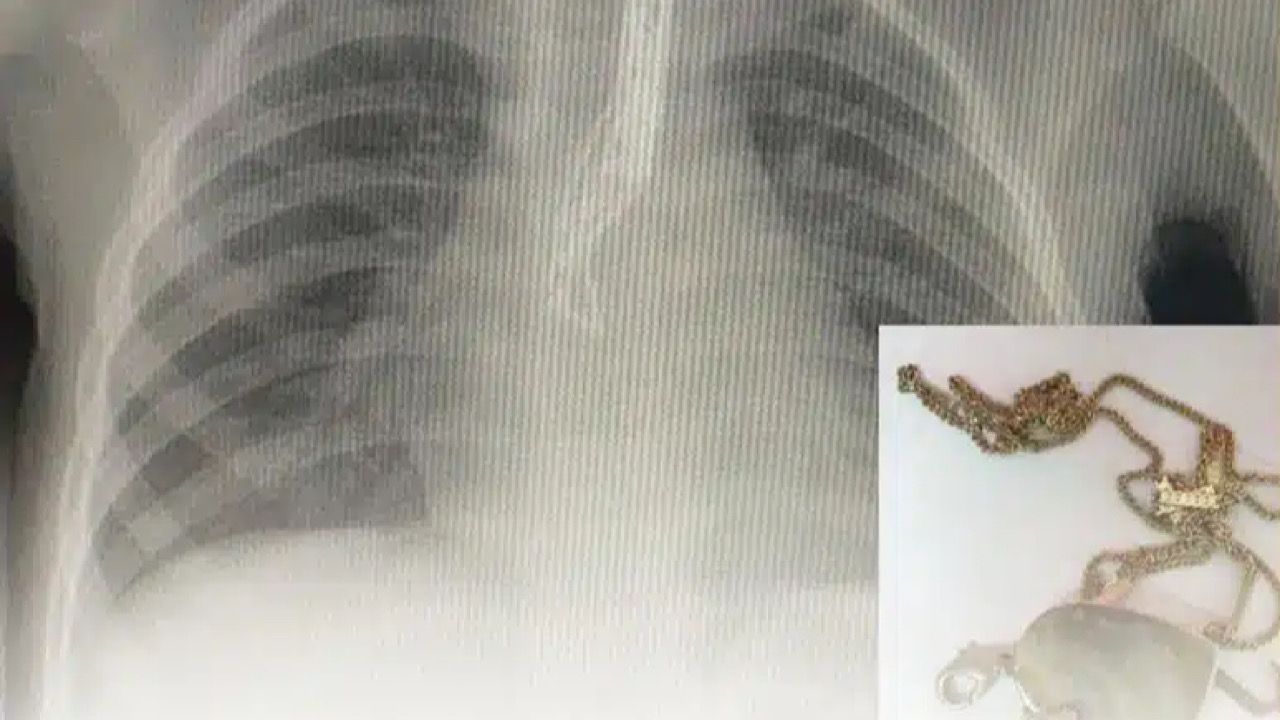

الفرق الطبية تنجح في إنقاذ حاجّة عراقيّة توقف قلبها لمدة 23 دقيقة